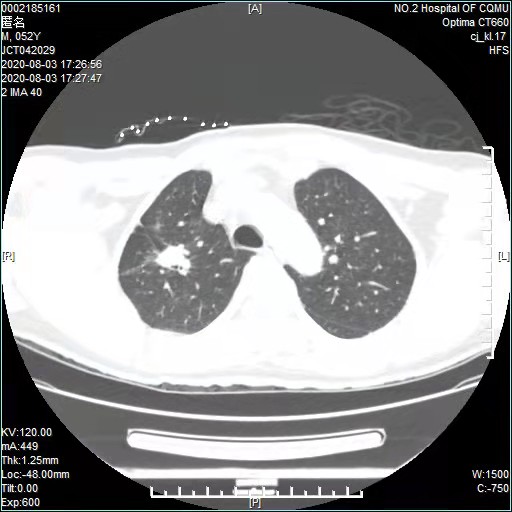

2019年10月,家住丰都的郑先生因不明原因的胸痛、咳嗽,来到重医附二院找到江德鹏诊治。通过CT等检查,明确诊断为肺腺癌,伴淋巴结、骨转移,情况不容乐观。

(术前)

看着一筹莫展的郑先生和他妻子,江德鹏教授安慰他们不用怕,详细解释了肺癌治疗的各种方法,因不适合手术治疗,同时经过基因筛查,发现明确有基因突变后,制订靶向药物联合抑制血管生成药物的治疗方案,同时辅以锶89等治疗。3个月后,认真配合治疗的郑先生复查,肿瘤显著缩小了,病情处于相对稳定状态。